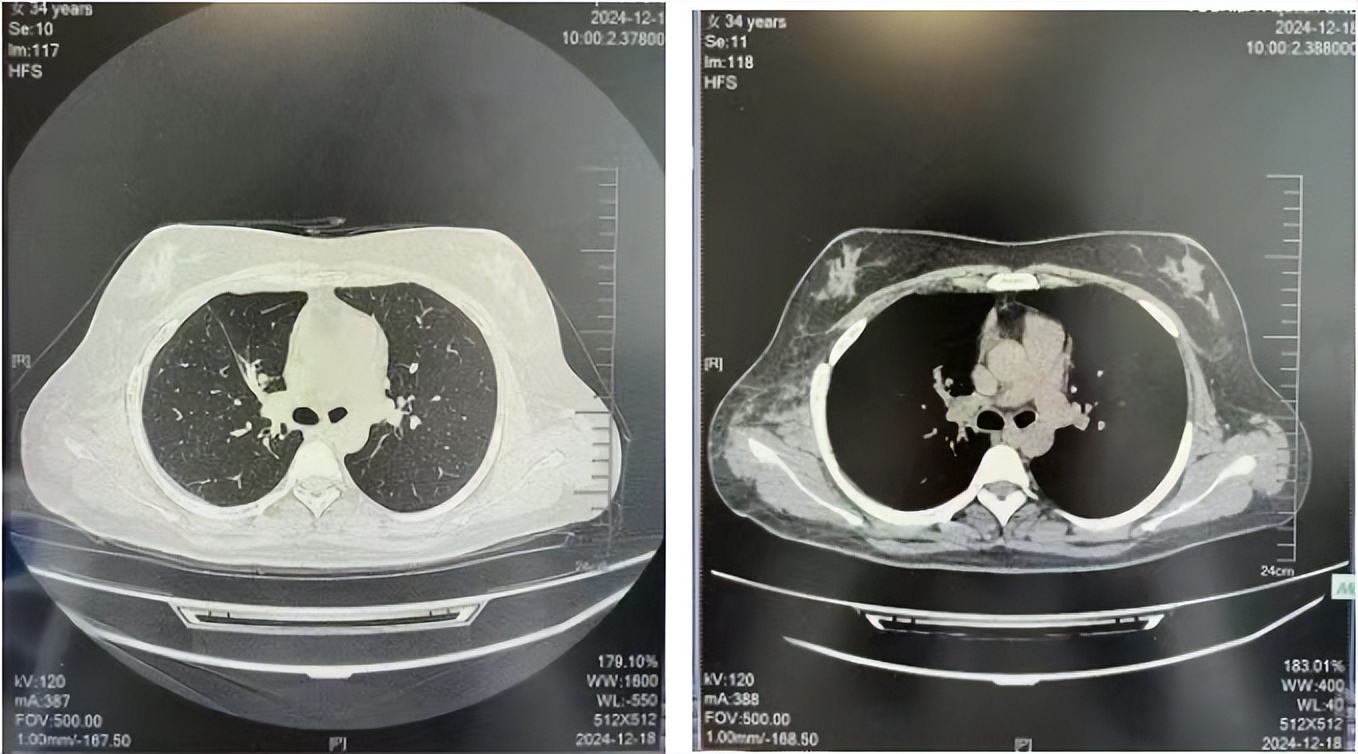

2024.12

2016年1月复查CT提示支气管截断可见新发小结节,一线治疗采用培美曲塞+DDP方案化疗4周期(培美曲塞3.36,DDP 480mg)。化疗后复查胸部CT:右肺见不规则结节样影,最大层面大小约19mm*8mm,较前比较明显增大,疗效评估PD。2017.3-2017.4予单药多西他赛化疗3周期,疗效评估SD。2018年5月末复查CT提示结节较前增大,评效为PD,2018年6-10月予多西他赛+CBP化疗4周期,疗效评估SD。2022年5月患者出现活动后气短,复查胸部CT示右肺膨胀不良;右侧胸腔积液增多。胸腔积液包埋病理示符合肺腺癌细胞。行NGS基因检测:EML4:exon13-ALK:exon20融合。PD-L1(克隆号22C3)TPS<1%。

临床诊断:右肺上叶恶性肿瘤rT0N0M1a IVA期(第9版分期);恶性胸腔积液。

诊疗经过:2022年5月始口服克唑替尼3个月,出现肝功能异常(DILI 2级伴临床症状),改用恩沙替尼靶向治疗至今,目前评效为维持PR。恩沙替尼应用期间出现轻度肝功能异常(DILI 1级),对症处理后好转。截止目前PFS 33个月。